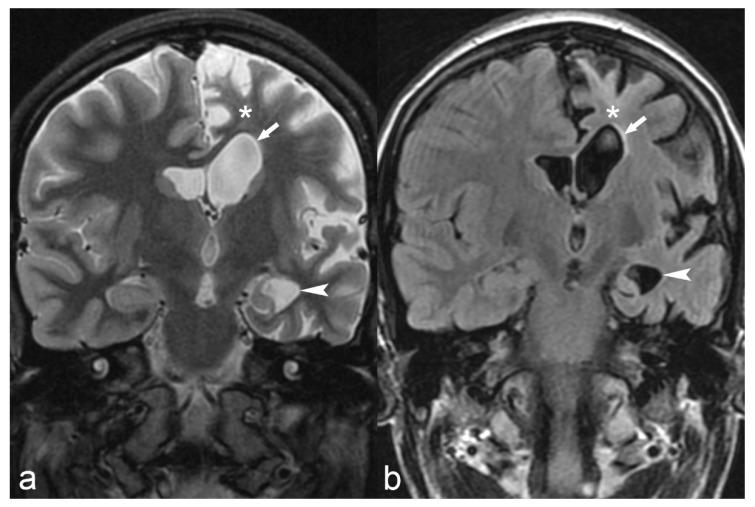

The etiology of epilepsy is variable and sometimes multifactorial. Clinical course and response to treatment largely depend on the precise etiology of the seizures. Along with the electroencephalogram (EEG), neuroimaging techniques, in particular, magnetic resonance imaging (MRI), are the most important tools for determining the possible etiology of epilepsy. Over the last few years, there have been many developments in data acquisition and analysis for both morphological and functional neuroimaging of people suffering from this condition. These innovations have increased the detection of underlying structural pathologies, which have till recently been classified as "cryptogenic" epilepsy. Cryptogenic epilepsy is often refractory to anti-epileptic drug treatment. In drug-resistant patients with structural or consistent functional lesions related to the epilepsy syndrome, surgery is the only treatment that can offer a seizure-free outcome. The pre-operative detection of the underlying structural condition increases the odds of successful surgical treatment of pharmacoresistant epilepsy. This article provides a comprehensive overview of neuroimaging techniques in epilepsy, highlighting recent advances and innovations and summarizes frequent etiologies of epilepsy in order to improve the diagnosis and management of patients suffering from seizures, especially young patients and children.